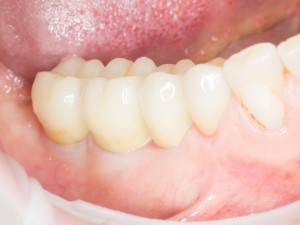

Почему всё это должен знать имплантолог? Дело в том, что суммарная длина конструкции «имплантат-абатмент-коронка» должна оставаться неизменной, если мы хотим, чтобы коронка была в прикусе и нормально функционировала. Это значит, что небольшая длина импланта должна быть компенсирована раздутым эго и большим джипом увеличением размеров супраструктуры, а именно — абатмента и коронки:

Но это еще не самое веселое. Допустим, мы решили проблему соединения «имплант-абатмент», у нас нет проблем с люфтами, а сам имплантат настолько хорошо интегрировался, что способен любую нагрузку в любом направлении. Возникает другая проблема — размер супраструктуры и соответствие ее нормальной биологической длине коронки зуба:

На фотографии выше, коронки опираются на обычные импланты, но даже в этом случае увеличение высоты супраструктуры усложняет гигиену и требует более пристального дальнейшего наблюдения. С ультракороткими имплантами, если честно, всё еще хуже.

Как будет выглядеть такая конструкция? Какой длины будут коронки? Возможно, на эстетику даже можно забить, ведь для некоторых людей красота зубов в боковом сегменте челюсти за пределами эстетически значимой зоны не так важна, но… как быть с уходом за протетической конструкцией и ежедневной гигиеной? Ведь, чем больше по размеру протез, тем сложнее за ним ухаживать. Тем больше мест, где может остаться зубной налет, а это, как вы понимаете, может привести к очень неприятным последствиям — периимплантиту, что для ультракоротких имплантов очень критично. А застревание пищи между протезом и десной? Можно ли назвать это «повышением качества жизни пациента»? Вряд ли.

В общем, уважаемые друзья, с точки зрения хорошего ортопеда, ультракороткие импланты — та еще задница. Да, для имплантолога работы меньше, поставить их очень просто, но вот когда доходит дело до протезирования, начинаются пляски с бубнами. А я. опять же, напомню, что мы должны выбирать такой план имплантологического лечения, чтобы максимально облегчить работу врачу-ортопеду. Чтобы он каждый раз, после приёма очередного пациента, делал так: